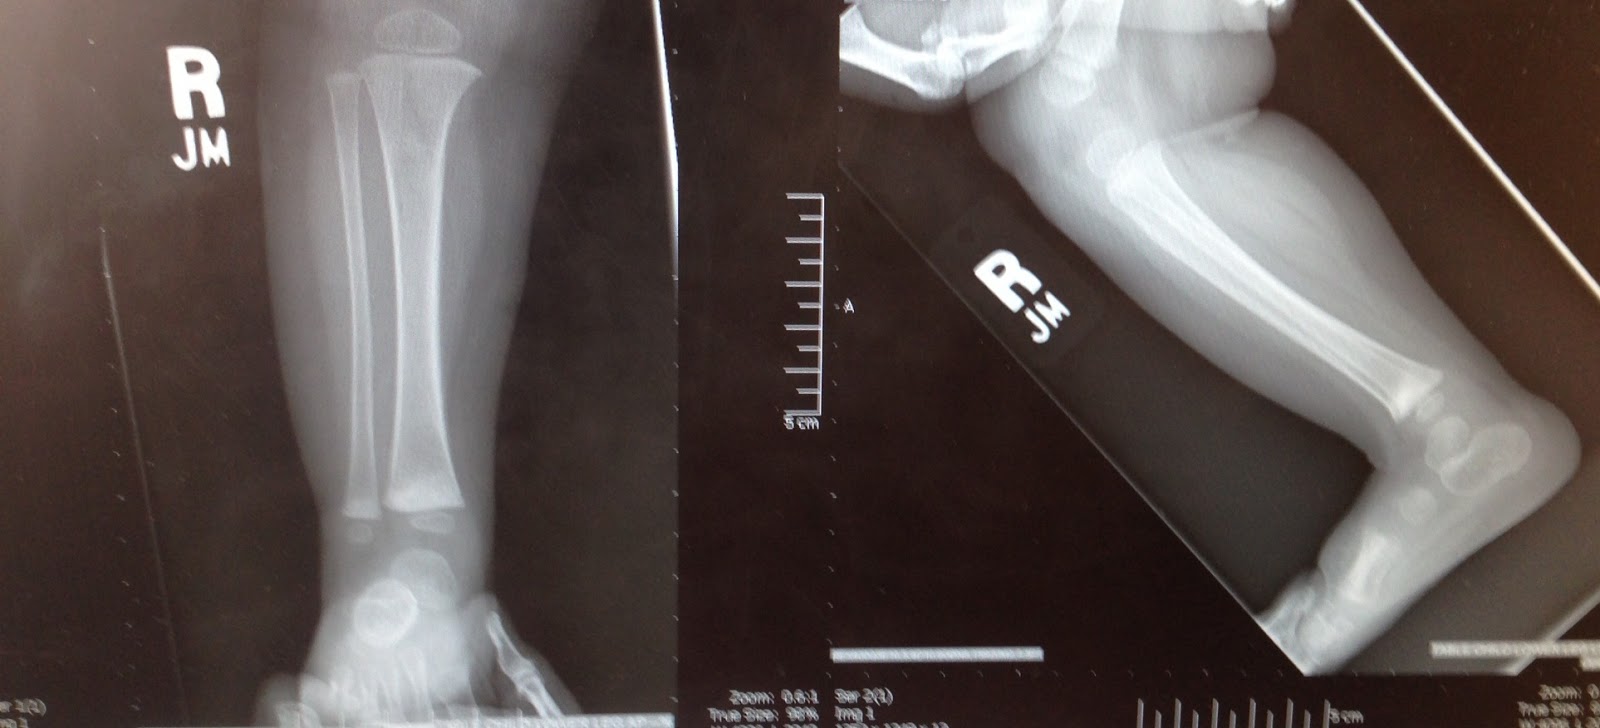

A few days later, our baby with a broken leg wanted to get up and walk. We tried hard for about 24 hours to keep her immobile, but FOR PETE’S SAKE, HAVE YOU EVER TRIED TO KEEP A ONE-YEAR OLD IMMOBILE? It was impossible. We decided to trust her, that she wouldn’t walk if it hurt, and we made an appointment to see a pediatric orthopedic surgeon when we got home, just to make sure her bone was healing properly. Due to some crazy circumstances, we didn’t get in to see the pediatriac surgeon until two weeks after the accident. He took new x-rays, and this is what he showed us:

Clara had, apparently, broken both of the bones in her lower right leg. The tibia and the fibula both had buckle fractures across the same line, probably a result of the way Sam held her tight against him when he fell. The surgeon said if he’d seen her after it happened, he would have cast her leg up to her hip, but it looked like her bones were healing perfectly even without any help, so he wasn’t going to give her a cast at all. It had only been two weeks, and her leg was almost completely healed. She hadn’t broken her growth plate (thank you Lord, that girl is already short enough) and he said she’ll be 100% in no time.

Whew! There you go, the long version of how these adorable x-rays came to be, and of our dramatic introduction to worrying about our children’s health and safety. But I mean seriously, have you ever seen an x-ray that is so damn cute?? Her leg chub, the miniature length of her calf… I melt.